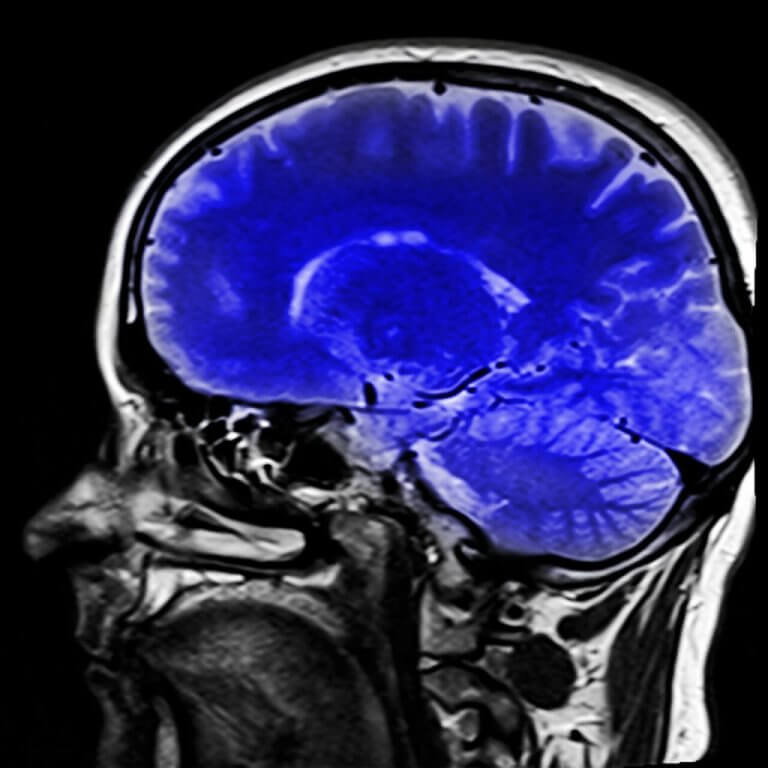

Läkaren kan använda sig av neurologiska test för att diagnostisera detta syndrom. Med hjälp av MRI kan man se vilken typ av stroke som har uppstått, och detta kommer hjälpa med diagnosen.